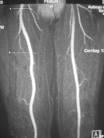

The company also announced today that ABLAVAR has been chosen as the brand name for gadofosveset trisodium. ABLAVAR (gadofosveset trisodium) is a blood pool contrast agent approved for magnetic resonance angiography to evaluate aortoiliac occlusive disease (AIOD) in patients with known or suspected peripheral vascular disease. The unique albumin-binding properties of ABLAVAR make it ideal for vascular imaging allowing multiple images to be obtained using a single, low dose injection. ABLAVAR enables the visualization of both arterial and venous blood vessels. ABLAVAR is clinically proven to produce high resolution MRA images, combining both dynamic (first pass) and steady state imaging, resulting in diagnostic accuracy comparable to X-ray angiography, the current standard of care for diagnosing vascular disease such as AIOD.

ABLAVAR is indicated for use as a contrast agent in magnetic resonance angiography (MRA) to evaluate aortoiliac occlusive disease (AIOD) in adults with known or suspected peripheral vascular disease.

The second oral presentation, “A Re-analysis of MS-325 (Gadofosveset Trisodium) Clinical Trial Data in Support of U.S. FDA Approval,” was given by Edward Parsons, Ph.D., formerly of EPIX Pharmaceuticals Inc. and currently a consultant to Lantheus Medical Imaging Inc. This presentation, which reported a blinded, independent re-read of images from previous phase 3 studies, found that ABLAVAR demonstrated statistically greater sensitivity (detecting disease when present) compared with noncontrast MRA. The study also showed that ABLAVAR had noninferior specificity (excluding disease when not present) with noncontrast MRA1. Thus ABLAVAR MRA images provided diagnostic accuracy superior to non-contrast MRA and comparable to traditional X-ray angiography."